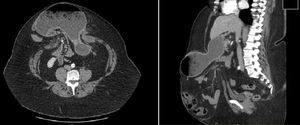

Actualmente presenta eventración de laparotomía media, causante de varios ingresos hospitalarios por suboclusión intestinal, resueltos conservadoramente. En TC abdominal se observa eventración gigante que contiene cuerpo y antro gástrico y asas de intestino delgado sin signos de complicación (fig. 1).

DiagnósticoEventración gigante con cuerpo y antro gástrico y asas de intestino delgado sin signos de complicación.